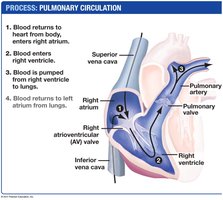

Cardiac Cycle and Blood Flow

The cardiac cycle consists of alternating periods of contraction (systole) and relaxation (diastole), ensuring unidirectional blood flow through the heart and to the body.

Systole: Ventricular contraction pumps blood into arteries.

Diastole: Heart relaxes and fills with blood.

Valves prevent backflow and produce the characteristic "lub-dup" heart sounds.

The heart's rhythmic contractions are initiated and coordinated by pacemaker cells in the sinoatrial (SA) node, with signals relayed through the atrioventricular (AV) node and specialized conduction fibers.

Intercalated discs and gap junctions allow rapid electrical signal transmission between cardiac muscle cells.